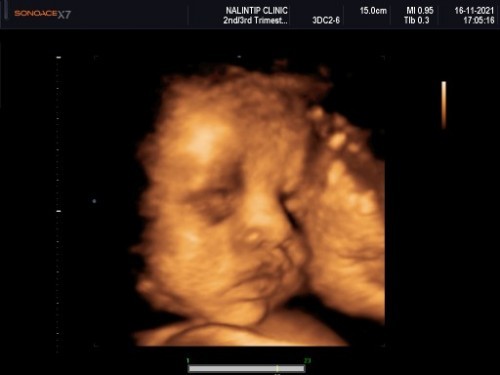

สวัสดีค่ะแม่บ้านนี้ 32w3วันแล้วค่ะ

Post reply image